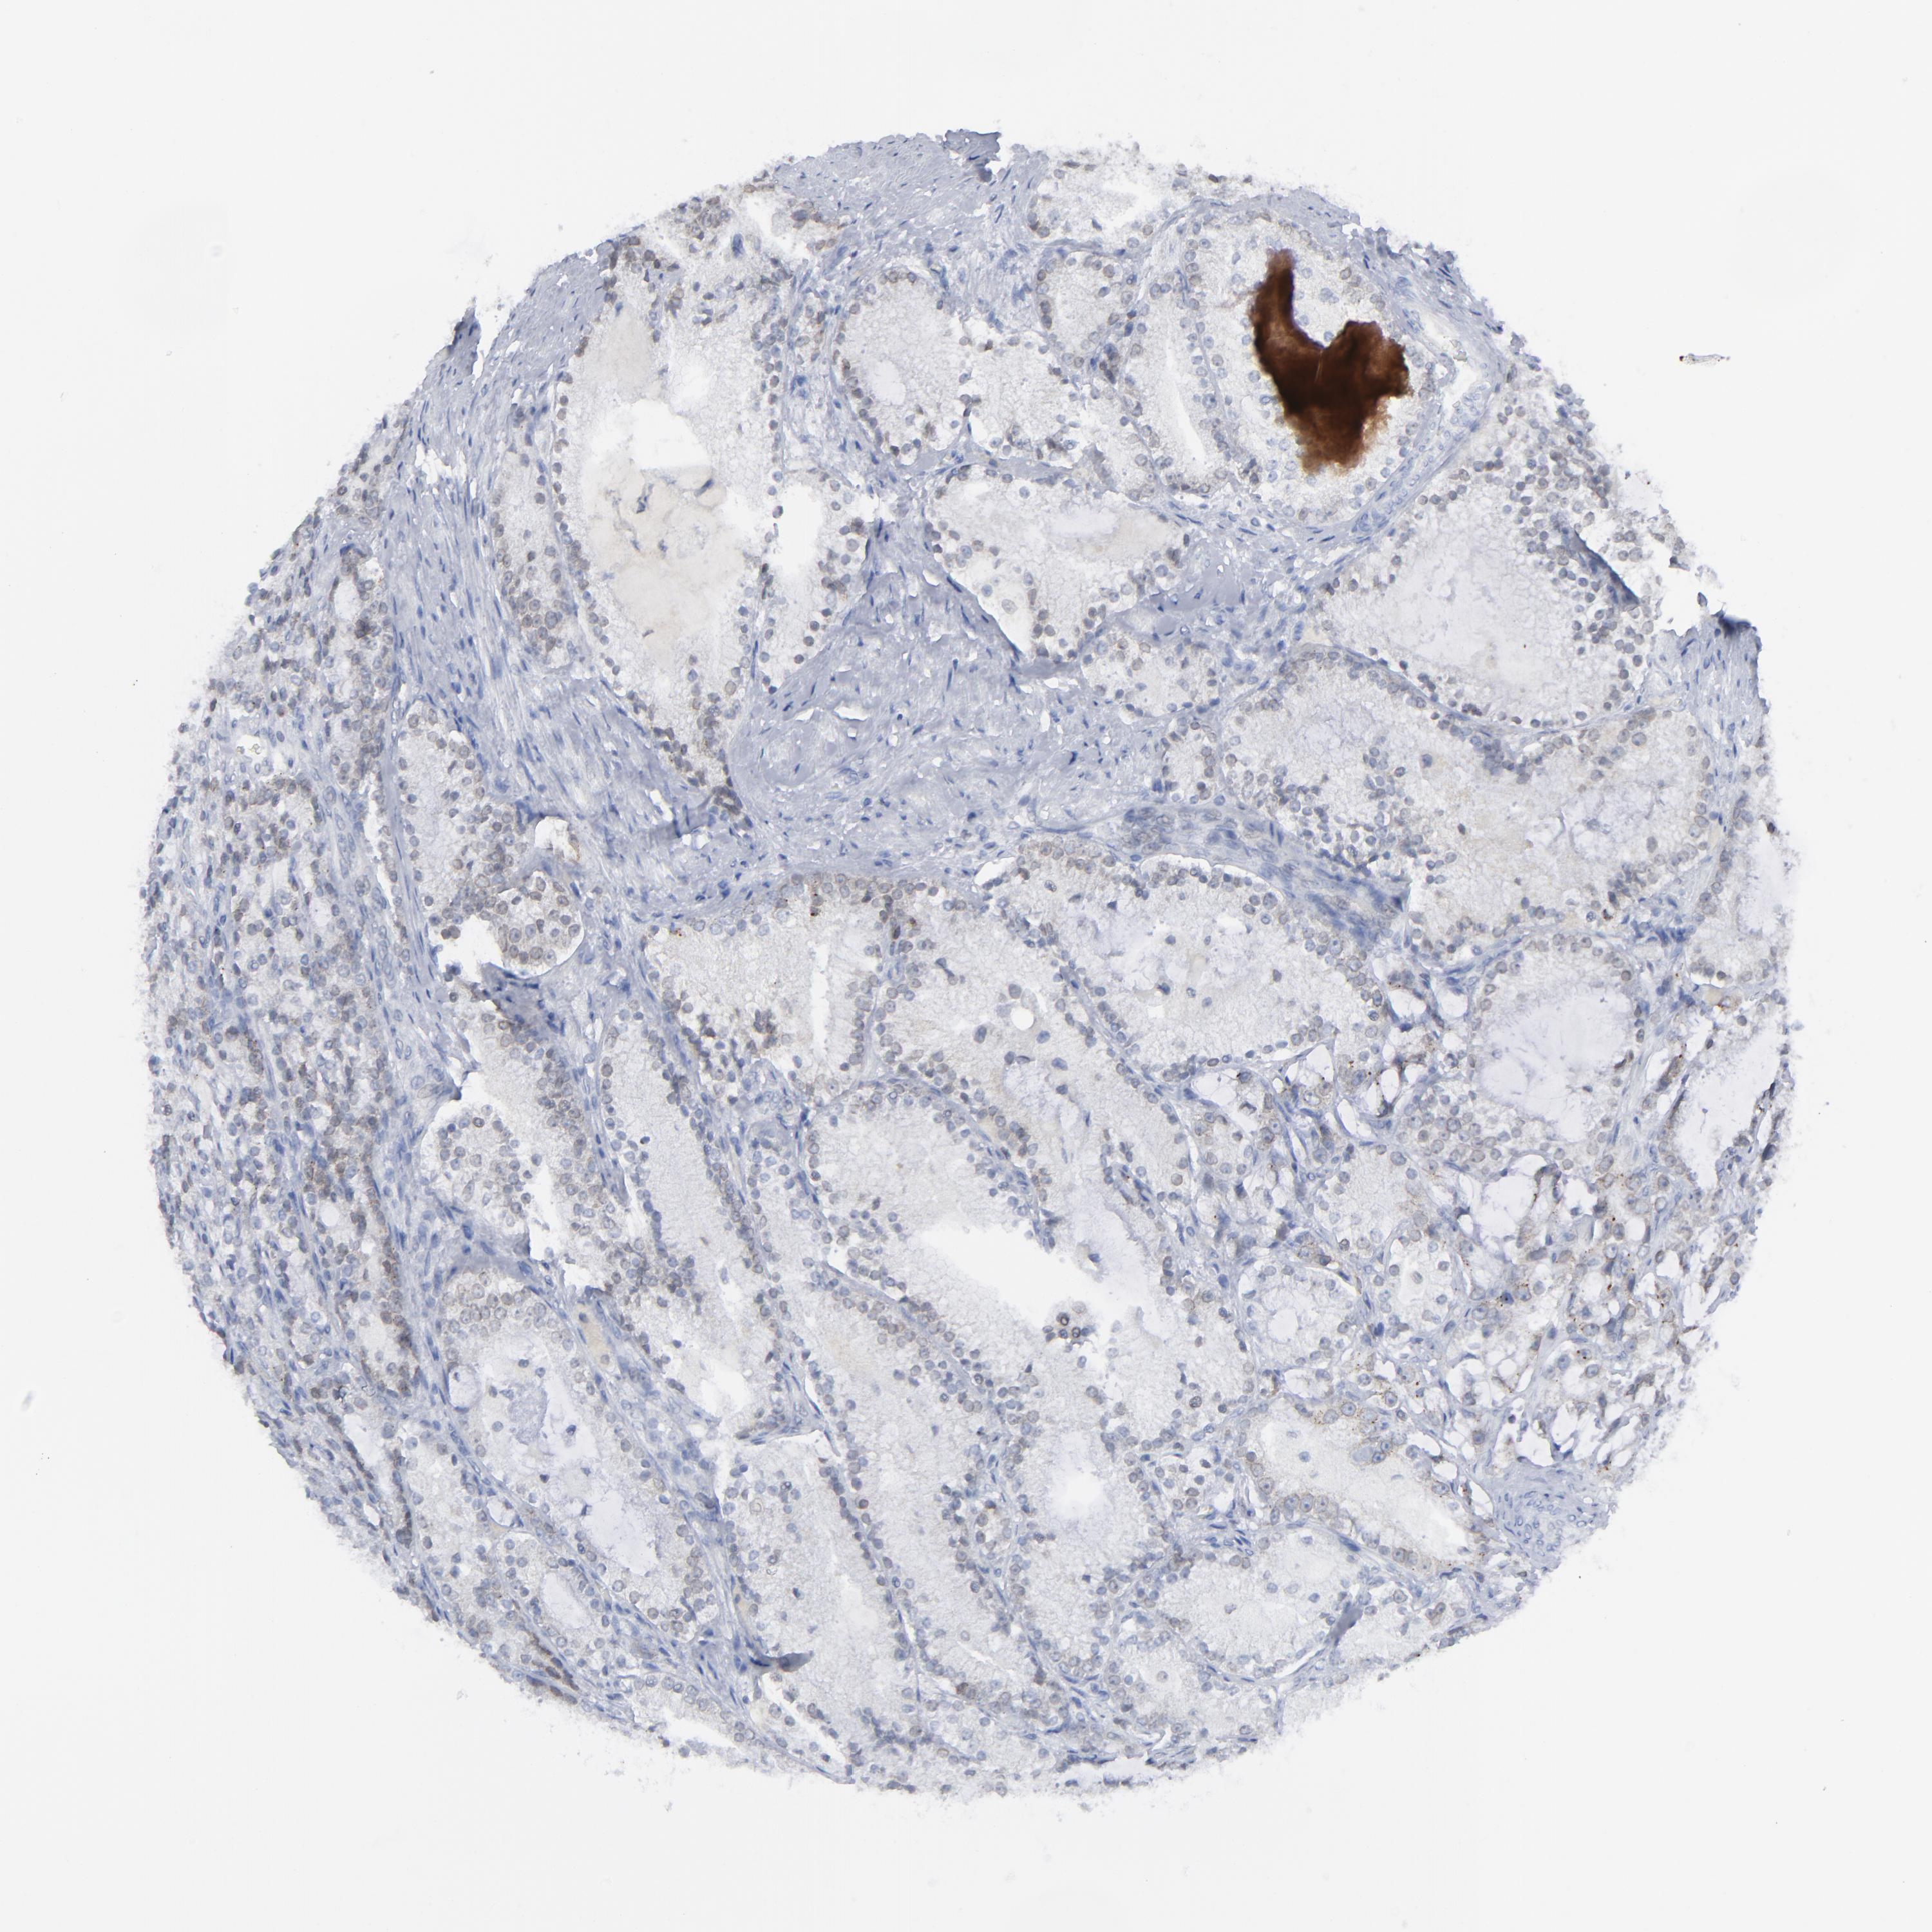

PROSTATE CANCER - Protein expressioni

A mouse-over function shows sample information and annotation data. Click on an image to view it in a full screen mode. Samples can be filtered based on level of antibody staining by selecting one or several of the following categories: high, medium, low and not detected. The assay and annotation is described here.

Antibody stainingi

Antibody staining in the annotated cell types in the current human tissue is reported as not detected, low, medium, or high, based on conventional immunohistochemistry profiling in selected tissues. This score is based on the combination of the staining intensity and fraction of stained cells.

Each image is clickable and will lead to virtual microscopy that enables deeper exploration of all samples and also displays staining intensity scores, fraction scores and subcellular localization as well as patient and tissue information for each sample.

Antibody HPA021816

Antibody CAB002209

Staining

High

Medium

Low

Not detected

Intensity

Strong

Moderate

Weak

Negative

Quantity

>75%

75%-25%

<25%

None

Location

Nuclear

Cytoplasmic/membranous

Cytoplasmic/membranous,nuclear

Adenocarcinoma, High grade

Adenocarcinoma, Low grade

Adenocarcinoma, Medium grade